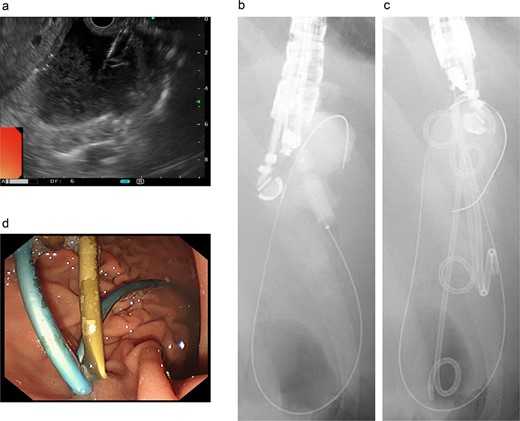

On the fifth day, the ascitic fluid increased in volume, and an open distal pancreatectomy was considered. However, her condition was stable. CT-guided abdominal drainage was performed, and a 10 Fr drainage tube was inserted for peritoneal lavage (Fig. 4). EUS-guided transgastric drainage of the pseudocyst in the omental bursa was performed. The pseudocyst was punctured; a balloon was dilated through the posterior wall of the stomach (Fig. 5a–c), and three tube stents of 7 Fr were implanted (Fig. 5d). The Amy and P-Amy levels in ascites were 9429 and 8877 IU/L, respectively; then, peritoneal lavage was performed daily. On the 12th day, contrast-enhanced CT revealed reduced pseudocyst size (Fig. 6). The patient was discharged on the 16th day (Fig. 7). Three years later, the patient is living her daily life without any complications.

Endoscopic ultrasound-guided transgastric pseudocyst drainage. (a) Endoscopic ultrasound-guided puncture of the pseudocyst. (b) The posterior wall of the stomach was punctured, and the puncture hole was dilated with a balloon. (c) Placement of three tube stents through the puncture hole. (d) Placement of three tube stents of 7 Fr-7 cm and 7 Fr-4 cm × 2.